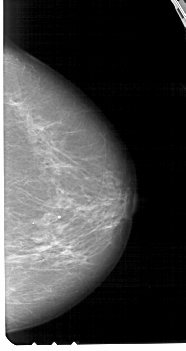

A_1442_1.LEFT_CC

LEFT_CC LINES 5491 PIXELS_PER_LINE 3031 BITS_PER_PIXEL 12 RESOLUTION 43.5 OVERLAY